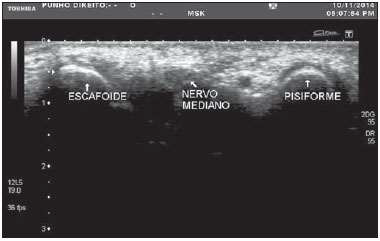

O.P.N, 60 anos, sexo feminino, costureira, obesa, hipertensa, diabética e moradora de Tracunhaém-PE, é encaminhada ao consultório de neurocirurgia com queixa de dor, dormência e formigamento em punho e dedos da mão direita que piora no fim do dia há 06 meses e com perda de força há 01 semana. É destra e relata episódios semelhantes nos últimos 06 meses, em especial quando precisa trabalhar muito. Trouxe resultado de ultrassonografia do punho direito com o diagnóstico de Síndrome do Túnel do Carpo (STC).

Assinale a alternativa INCORRETA.